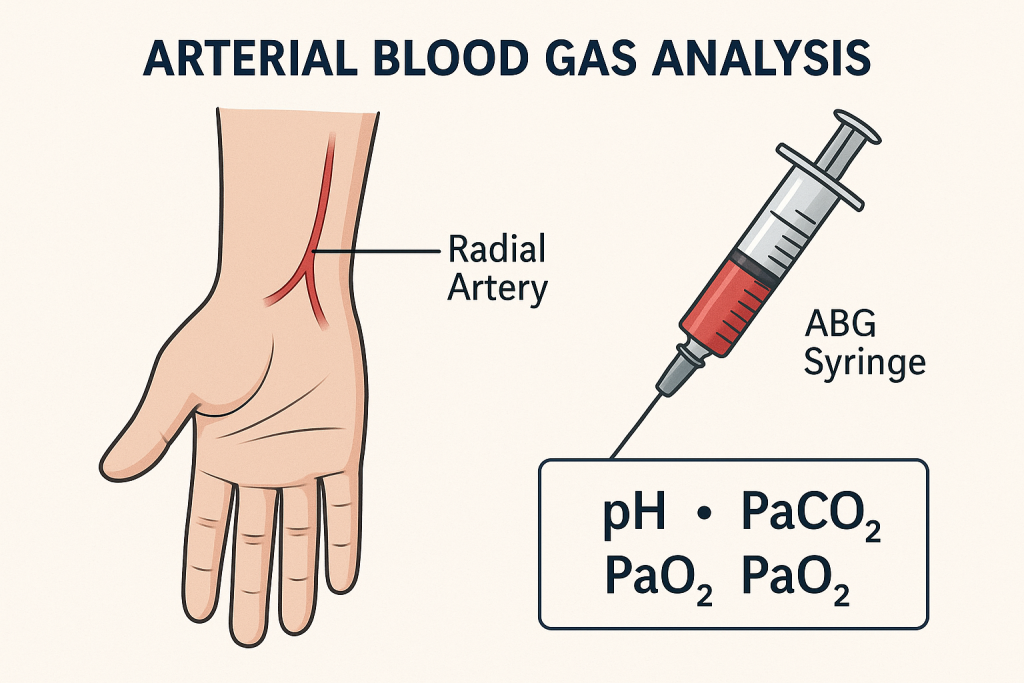

Arterial blood gas analysis (ABGs) (આર્ટીરિયલ બ્લડ ગેસ એનાલાયસીસ):

- આર્ટીરિયલ બ્લડ ગેસ એનાલાયસીસ એ એક ઇમ્પોર્ટન્ટ ડાયગ્નોસ્ટિક મેથડ છે. જે બ્લડમાં રહેલ ઓક્સીજન અને કાર્બન ડાયોક્સાઇડનું લેવલ મેઝર કરવામાં આવે છે તેમજ બ્લડ PH અને બ્લડ બાયકાર્બોનેટનું લેવલ પણ મેઝર કરવા માટે ઉપયોગી છે.

- જેમાં મુખ્યત્વે એક્સપર્ટ હેલ્થ કેર પર્સનલ દ્વારા રેડિયલ આર્ટરીમાંથી બ્લડ કલેક્ટ કરવામાં આવે છે આ ઉપરાંત ઘણીવાર બ્રેકીઅલ અથવા ફીમોલર આર્ટરીમાંથી પણ બ્લડ કલેક્ટ કરવામાં આવે છે. (વેઇનમાંથી બ્લડ કલેક્ટ કરવામાં આવતું નથી)

- આ ટેસ્ટ દ્વારા લંગની બ્લડમાં ઓક્સિજન ડીઝોલ્વ કરવાની અને બ્લડમાંથી કાર્બન ડાયોક્સાઇડને રીમુવ કરવાની કેપેસિટી કેટલી છે તે જાણી શકાય છે.

- આ ટેસ્ટ કરતા પહેલા એલેન ટેસ્ટ કરવામાં આવે છે જે હેન્ડમાં બ્લડ સપ્લાય કરતી આર્ટરીની (રેડીયલ અને અલ્નાર આર્ટરી) પેટેન્સી ચેક કરવા માટે વપરાય છે. Normal value of ABGs (નોર્મલ વેલ્યુ ઓફ ABGs)